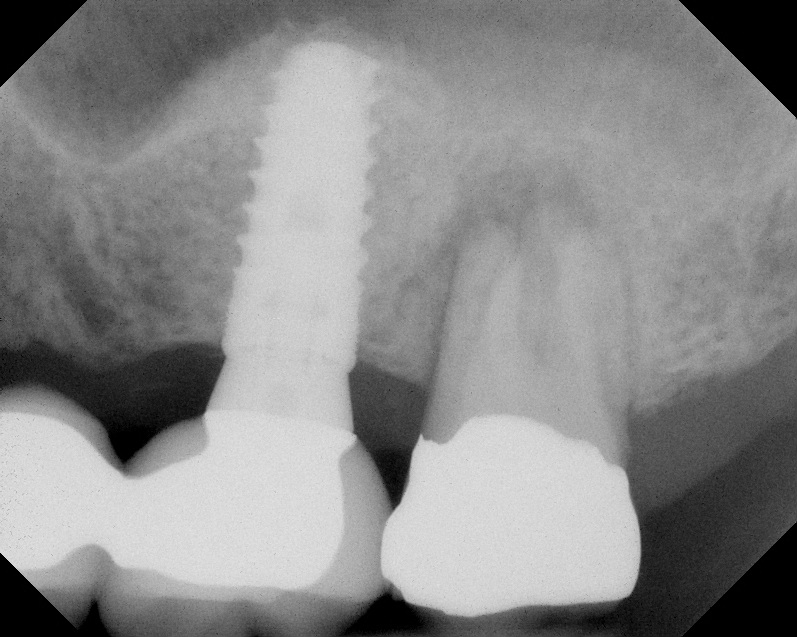

As with implant placement in general, use of a round bur is the first step in forming the osteotomy. As described above, to get verification of positioning—especially if a surgical stent is not used—a small piece of gutta percha can be placed inside this small osteotomy and a radiograph taken (Figure 1), after which the gutta percha is removed. The next step is the most critical, as it involves exposing the Schneiderian membrane. A 2-mm twist drill is used at a speed not exceeding 250 rpm, using a very light touch. Because the bone quality in the maxillary posterior is generally poor, it is usually easy to feel when the medullary bone has been breached and the dense cortical bone of the floor of the sinus has been reached. The cortical plate of the floor of the sinus should have been carefully measured with periapical radiographs presurgically, but it is usually about 1 mm in thickness. The most important and technique-sensitive part of this procedure is breaching the cortical plate of bone lining the sinus without tearing the sinus membrane. With a solid finger rest, good control, very light drilling pressure, copious irrigation, and a slow drilling speed, a slight “give” occurs once this plate of bone is breached. The full width of the twist drill should not penetrate the sinus floor; otherwise, the membrane will be torn. If it is not clear whether the membrane has been exposed, a flat-ended implant probe (Figure 2) can be used by inserting it into the osteotomy and feeling for the slight “give” or movement of the membrane. If the surgeon is not sure if the membrane is exposed, a radiographic marker can be used (Figure 3). If the membrane is significantly exposed, however, a radiographic marker should not be used, as this can inadvertently tear the membrane. The patient should also be warned not to bite down on the marker during the radiograph to avoid a membrane tear, and floss must be attached to the marker, so it can be retrieved if necessary.

Because the bone grafting materials used in this technique need physical stability during healing to support the raised membrane, there is a high probability that significant shrinkage of the graft will occur as it heals and matures if only non-demineralized material is used. For these reasons, a composite graft using calcium sulfate, DFDBA, and mineralized particulate bone is used. A 50:50 mixture by volume of mineralized bone grafting material and DFDBA is used, to which approximately 40% calcium sulfate by volume is added. A higher percentage of calcium sulfate is used relative to that described for composite grafting in other uses, because some of the calcium sulfate will wash out during bone packing. Another advantage to this composite graft is that it is not as radiopaque as a purely mineralized graft. This allows radiographic monitoring of the bone healing around the implant, which can be used to time abutment placement on the implant. This is demonstrated in Figure 4 and Figure 5, which are radiographs taken on the day of the initial surgery showing the radiographic appearance of the composite graft, implant, and graft, and in Figure 6, a 5-month postoperative radiograph with the abutment in place. The old floor of the sinus is indistinguishable from the area of new bone. Figure 7 shows a CBCT scan (Carestream Dental, www.carestreamdental.com) taken at 4 months with the old floor of the sinus indistinguishable from the new bone formed.

After about seven or eight cycles, a radiograph should be taken to verify the apical position of the sinus membrane (Figure 4). If the sinus has been raised at least 3 mm to 4 mm, the 2.8-mm twist drill should be used to remove the remaining bone at the base of the osteotomy. The osteotomy should then be widened to the final twist drill but not yet the last drill, which is the profile drill. This will allow for easier bone tapping into the sinus. The desired height of sinus membrane elevation should be such that there is about 1 mm to 2 mm of additional apical height above the implant to be placed. Usually a 10-mm implant length is sufficient. The design of the implant should have threads close to the coronal aspect of the rough surface for better initial fixation. When using a tapered implant design, the final drill is a tapered profile drill, which is the last step before placing the implant. Because it is slightly longer than the actual implant, its use could tear the membrane. To minimize the chance of tearing the membrane, a high-speed round bur and copious irrigation can be used to flatten the end of the tapered profile drill by about 1.5 mm (Figure 9) before its use. It should be used at less than 200 rpm with limited irrigation. The groove on the profile drill corresponds to the level of the bone when used. If there is minimal native ridge height, the drill should be used to a lesser depth than the groove to make sure that the site is not drilled too deeply.

Radiograph showing the sinus membrane being elevated about 8 mm

supported by a composite bone graft that is partially radiolucent in the

No. 14 position.

Fig. 4

Radiograph of implant N o. 14 and graft in place, day of placement.

Fig. 5

Radiograph of implant N o. 3 and sinus augmentation, day of placement. There is about 2 mm to 3 mm of native bone, and the sinus has been raised about 8 mm to 9 mm.

Fig. 10

Radiograph of sinus composite bone augmentation in the No. 14 position.

Fig. 14

Radiograph of implant No. 14 with sinus augmentation, day of placement. The floor

of the sinus has been raised about 7 mm to 8 mm.

Fig. 15